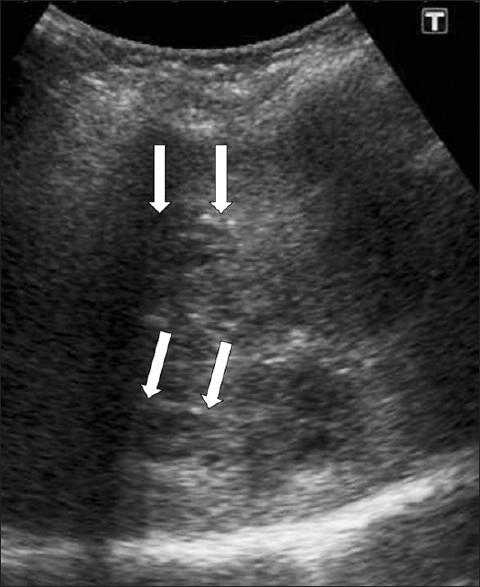

Fascioliasis refers to a zoonosis caused by Fasciola hepatica, a trematode infecting herbivores, but also occurs in humans who ingest the metacercaria found in fresh water plants. Infection in humans is common in developing countries and is also not uncommon in Europe. Diagnosis of this infection is difficult, as the history and symptoms are nonspecific and stool analysis for eggs is negative until the disease is in an advanced state by when the parasite has reached the biliary system. The clinical course consists of two phases; first a hepatic parenchymal phase in which immature larvae invade the liver parenchyma, followed by a ductal phase characterized by the excretion of larvae into the bile ducts. Parenchymal Phase: Ultrasonography (US) findings are nonspecific in this early phase. Computerized tomography (CT) may demonstrate subcapsular low attenuation regions in the liver. Magnetic Resonance imaging (MRI) can also be utilized to establish liver parenchymal involvement, and is better than CT in characterizing hemorrhagic lesions, as well as identifying more lesions relative to CT. Ductal Phase: US examination is most useful at this stage, with its ability to demonstrate the live movement of the worms within the dilated ducts. A CT demonstrates dilated central biliary ducts with periportal tracking, whereas, mild ductal dilatation is poorly appreciated under MRI. Therefore, familiarity with the multimodality imaging features of fascioliasis, in combination with an available confirmatory enzyme-linked immunoassay, would be most helpful for early diagnosis.

肝片吸虫病是一种由肝片吸虫引起的人畜共患病,这种吸虫感染食草动物,但人类摄入淡水植物中的囊蚴后也会感染。在发展中国家,人类感染这种疾病很常见,在欧洲也并不罕见。这种感染的诊断很困难,因为病史和症状不具有特异性,而且在疾病发展到晚期寄生虫进入胆道系统之前,粪便虫卵分析一直呈阴性。临床病程包括两个阶段:首先是肝实质期,未成熟幼虫侵入肝实质,随后是导管期,其特征是幼虫排入胆管。实质期:在此早期阶段,超声检查(US)结果不具有特异性。计算机断层扫描(CT)可能显示肝脏包膜下低密度区域。磁共振成像(MRI)也可用于确定肝实质受累情况,在表征出血性病变以及相对于CT识别更多病变方面比CT更好。导管期:US检查在这个阶段最有用,它能够显示扩张胆管内虫体的活动。CT显示中央胆管扩张并伴有门静脉周围条索状影,而在MRI下轻度胆管扩张不易被察觉。因此,熟悉肝片吸虫病的多模态影像学特征,并结合可用的确诊酶联免疫测定,对早期诊断最有帮助。